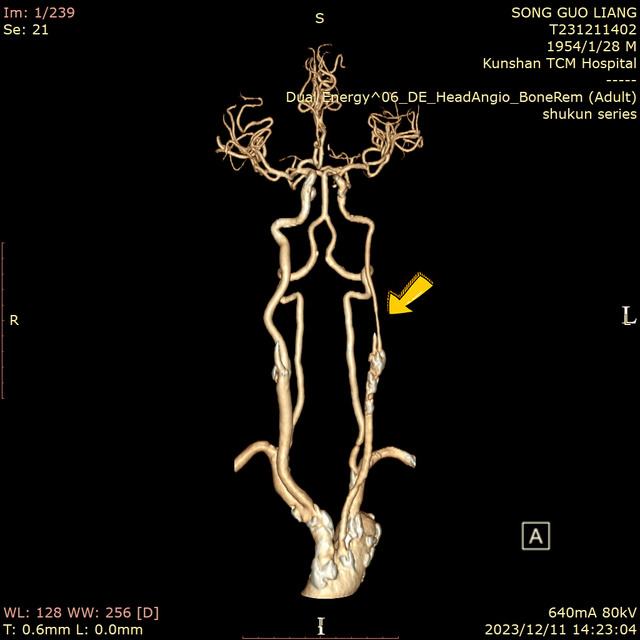

▲術(shù)前CTA檢查見患者主動脈弓、頸動脈多處粥樣硬化斑塊,左頸總動脈分叉處血管重度狹窄